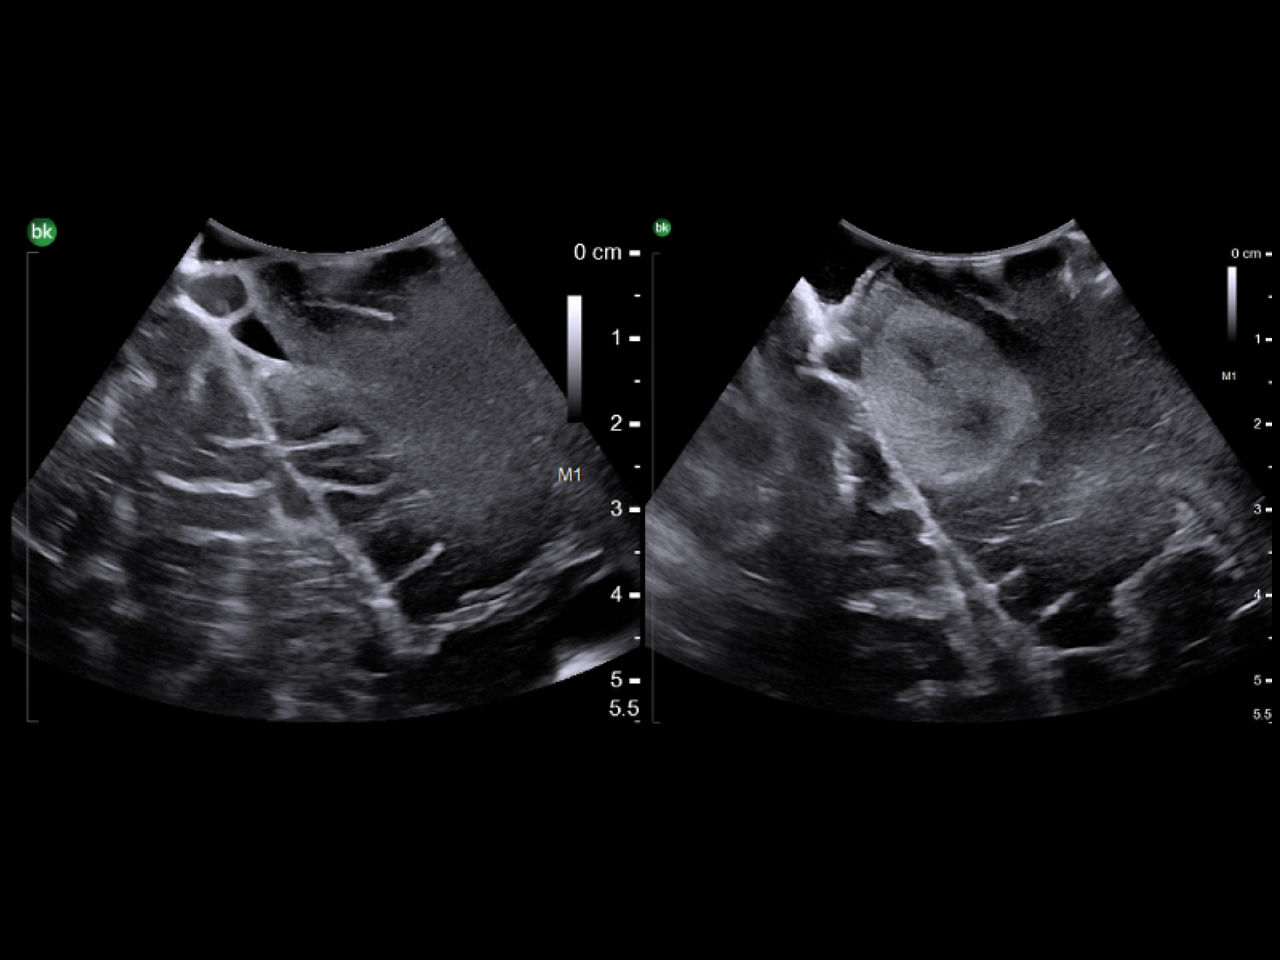

Neuro-oncology

Use intraoperative ultrasound during surgery to assist in the identification of brain shift after pre-operative scans and determine extent of resection and assess for residual tumor.

Skull base

Use intraoperative ultrasound during surgery to avoid injury by identifying blood vessels near the pituitary gland, access hard-to-reach areas and use through cranial endoports. With the bkPortfolio's smallest transducer monitor resection progress and assess for residual tumor.